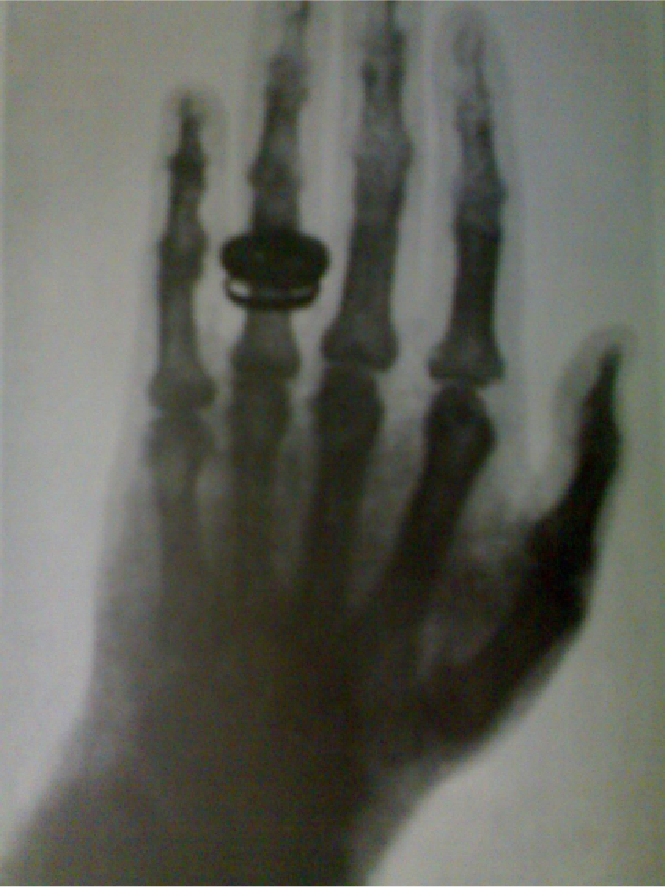

19世纪末,X射线的发现开创了核技术时代。随着社会的进步、科学的发展,人类对核技术的利用也在不断发展,实现了许多开创性的应用,如医学中的影响诊断、放射治疗,农业中的辐射育种、辐射杀菌,工业中的焊接探伤、辐射液位计,以及电力中的核能发电、核供热等。核技术的发展推动了人类文明的进步,成为我们日常生活中不可缺少的重要部分。